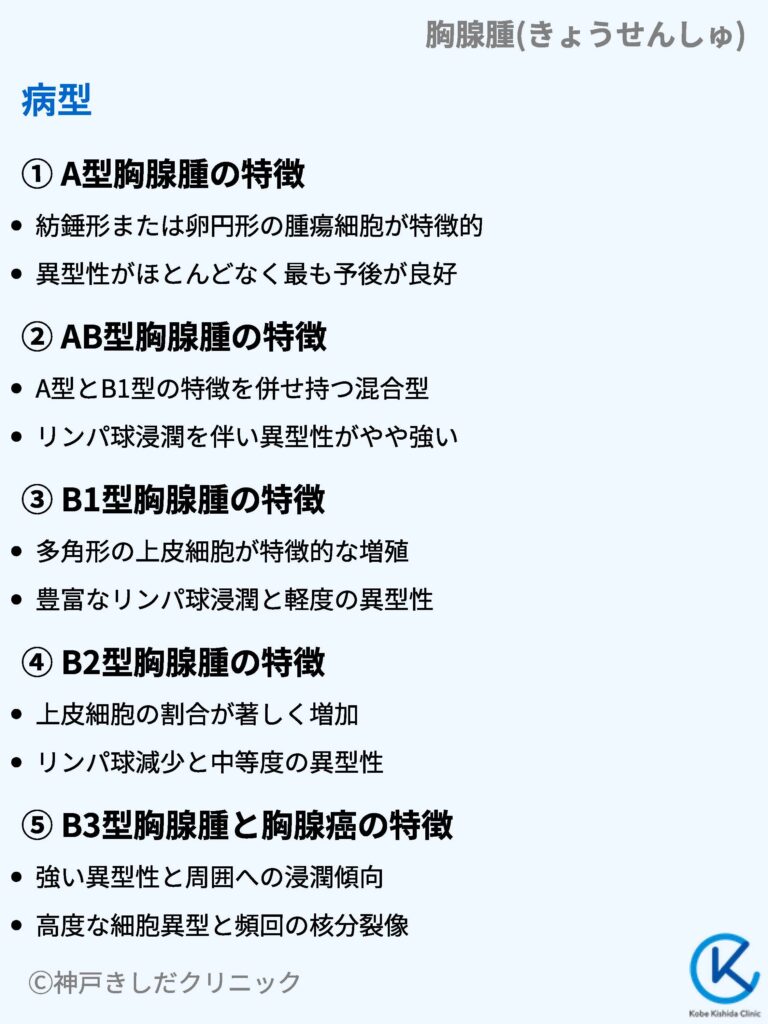

呼吸器系2,3-呼吸解剖1,2。縦隔腫瘍について | 新座志木中央総合病院。縦隔腫瘍|がん診療の特色と実績(院内がん登録)|診療体制。桂新堂 海老 えび せんべい。

※個人情報の記載がある場合は、サインペン等で塗りつぶした上で発送させていただきます。胸腺腫(きょうせんしゅ Thymoma) – 呼吸器疾患 - 神戸きしだ。